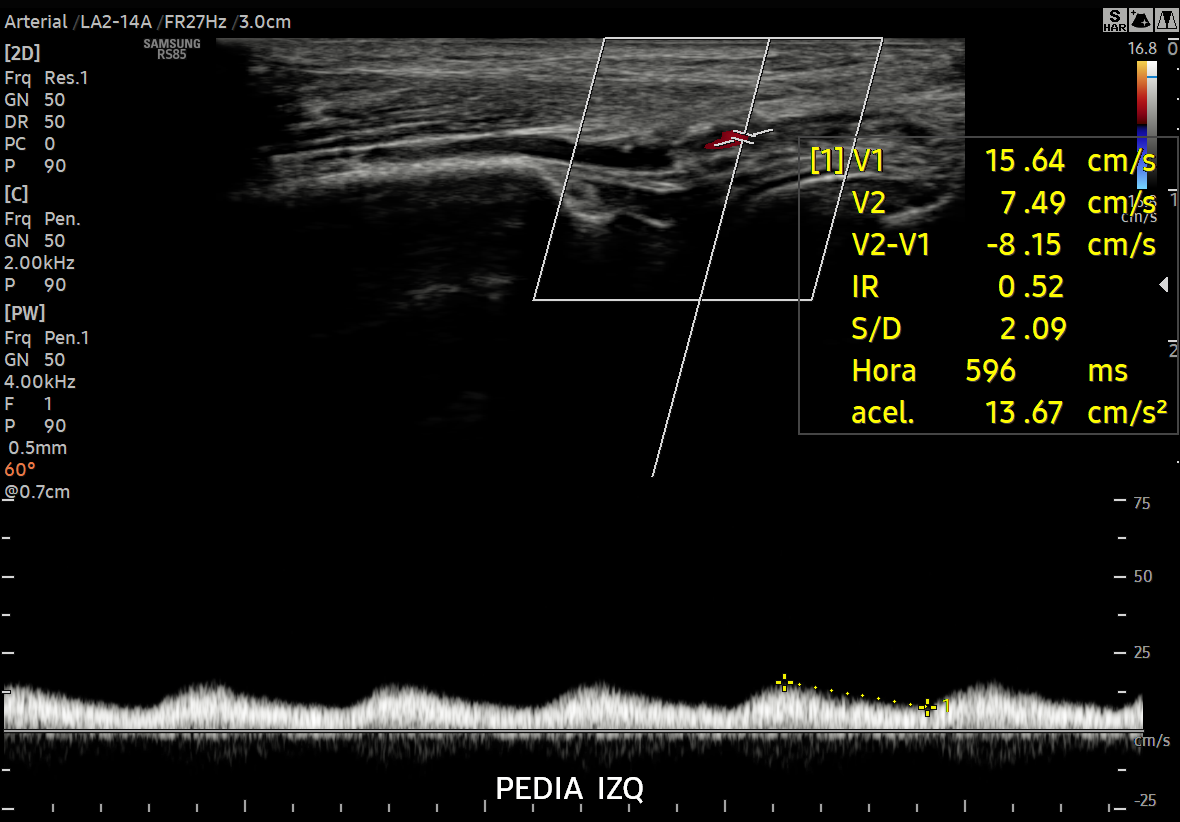

ECOGRAFÍAS Tiroides Abdomen Urológica Vascular Pediatría-Neonatal Músculo Esquelético Obstetricia 4D - 5D Ginecología Partes Blandas